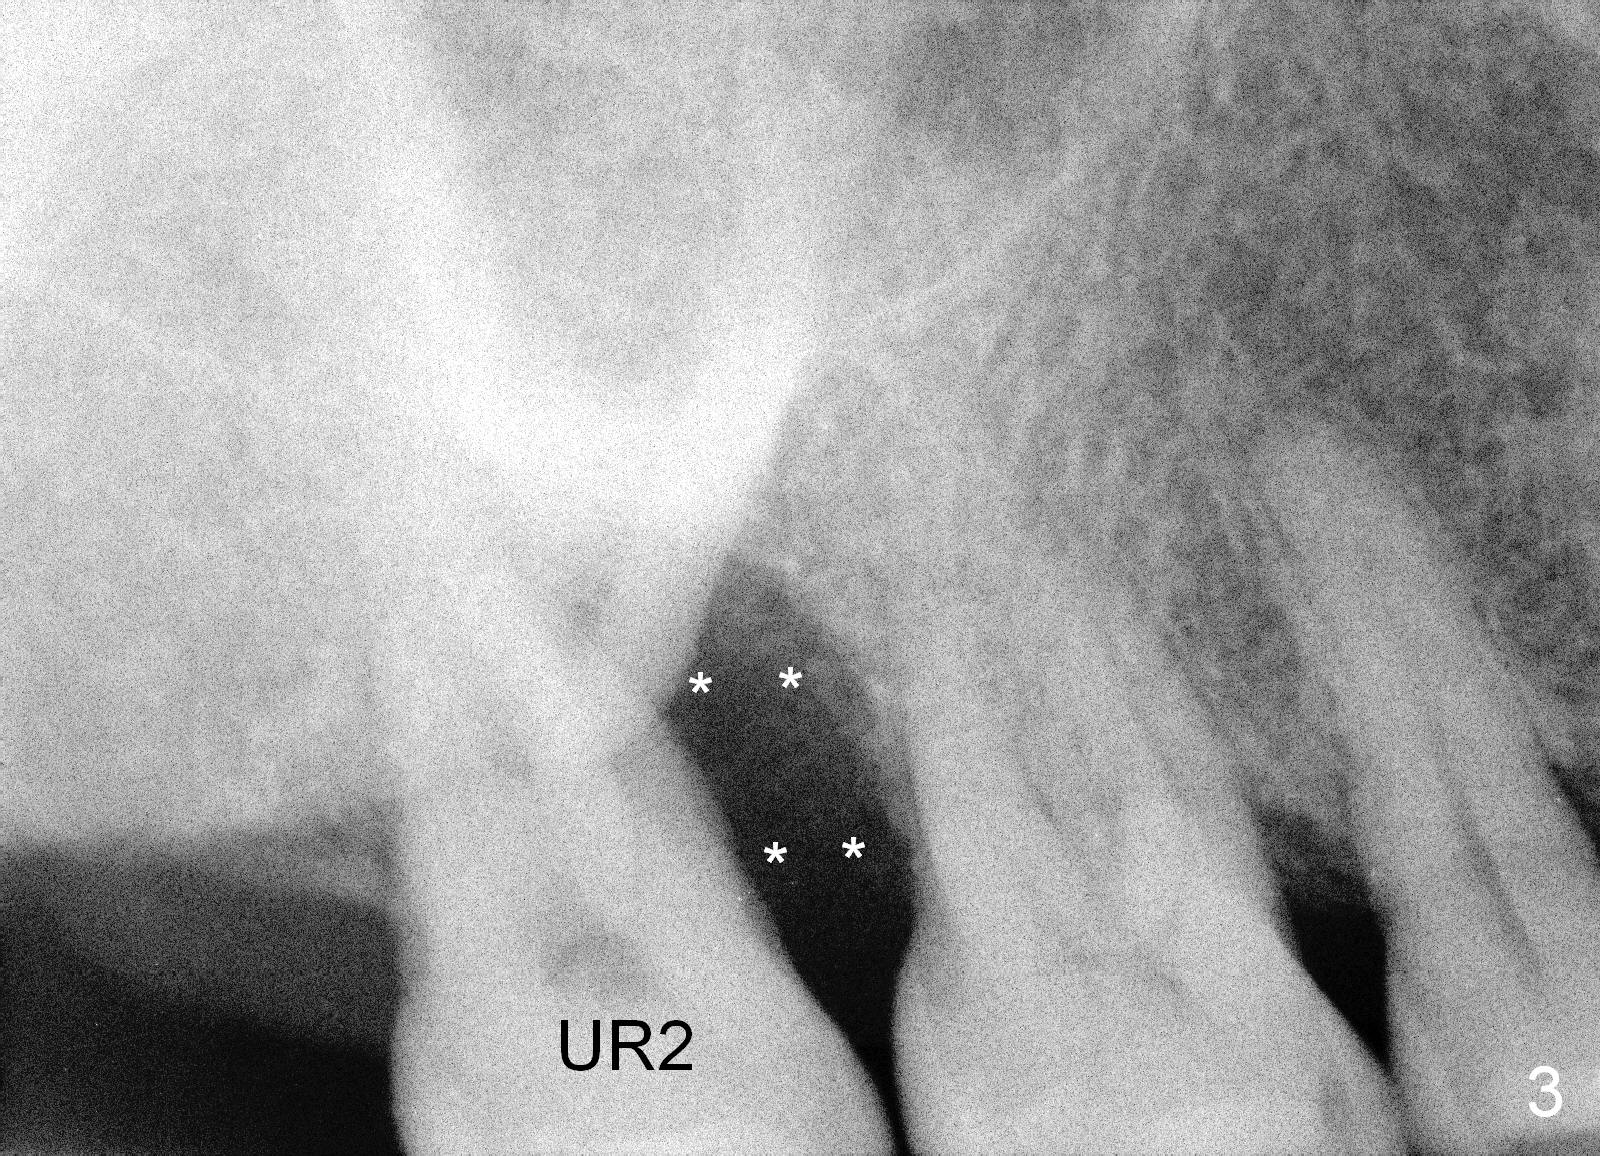

When she returns 7 years later, the tooth #2 has perio abscess with severe bone loss (Fig.3). She refuses to take antibiotic for infection control, but agrees to have immediate implant for #2 because of 1-staged surgery (Fig.5 I: 8x17 mm; A: abutment; P: bone powder (graft)). She is aware of delayed implants at the sites of #15 and 31 later. The bone height at the site of #15 reduces from 12 mm (Fig.4) to 7 mm (Fig.6) in 7 years.